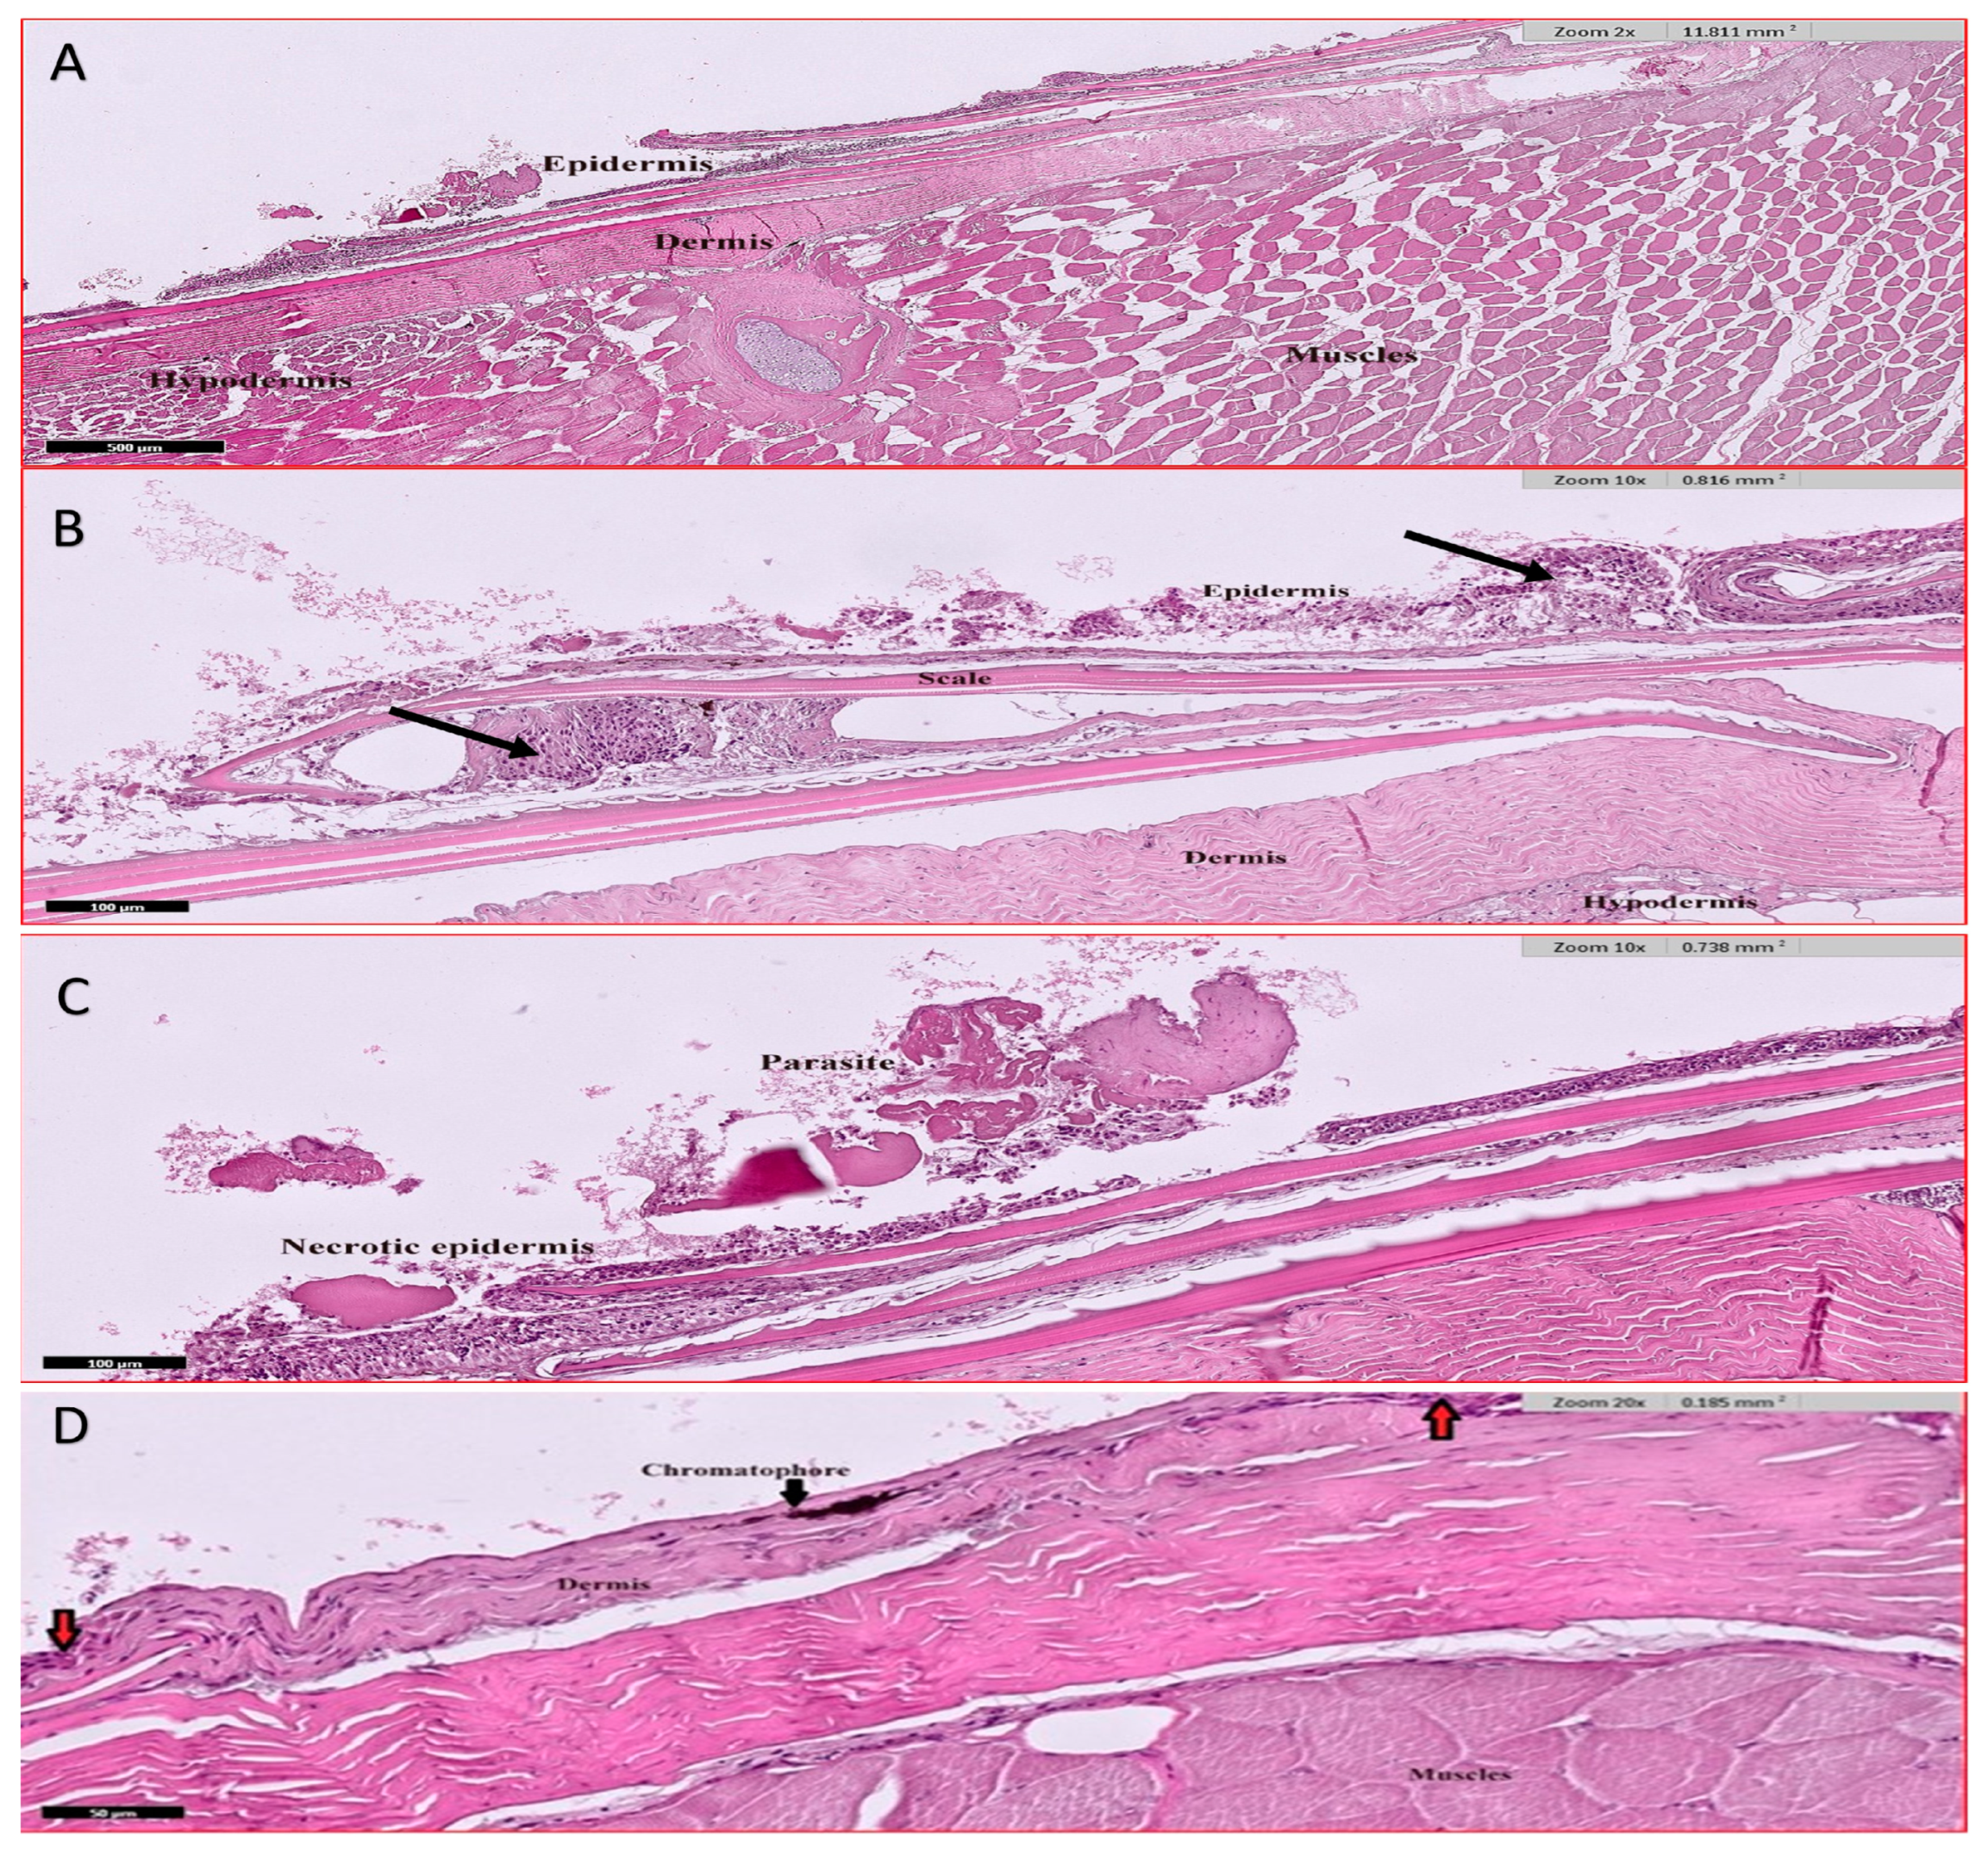

3.4.5. Skin